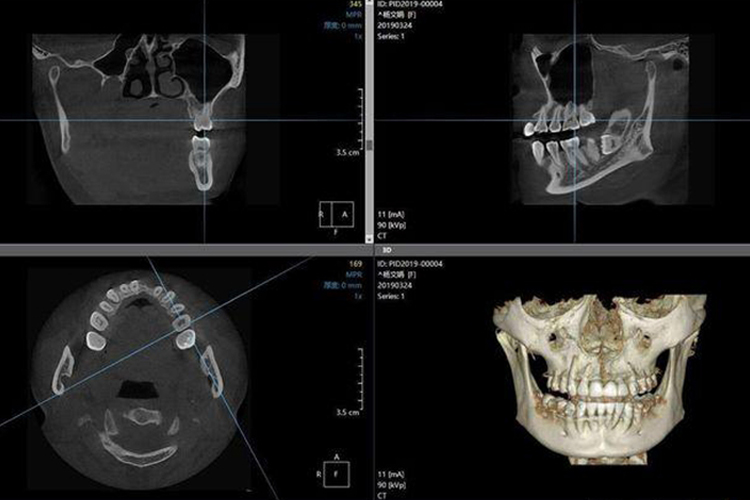

牙齿CT通常是指CBCT,即锥形束CT,标准锥形束CT可清楚显示患者颌骨、牙齿以及颞下颌关节等硬组织结构,在三维重建图像上通过调节窗去除部分骨组织,只留下密度更高的牙齿图像,可清晰显示骨内埋伏牙与邻牙空间位置关系。此外,CBCT还可拍摄口腔全景片,可以在一张全景图上观察全部牙齿的情况。